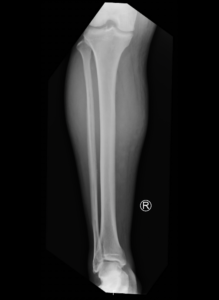

Acute Compartment Syndrome. XRay. JETem 2024